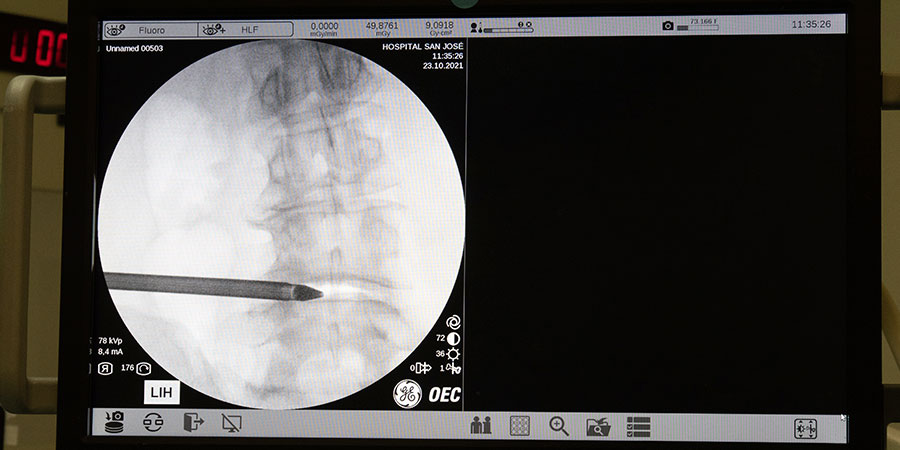

De la mano del Prof. Dr. Elgeadi, un innovador sistema quirúrgico de columna ha transformado las intervenciones de columna vertebral mediante técnicas y procedimientos con la tecnología más puntera y vanguardista. Más de 7.800 cirugías realizadas y más de 10.000 consultas al año avalan la experiencia de los expertos que forman parte del instituto de Cirugía Avanzada de Columna, reconocidos a nivel nacional e internacional como pioneros en cirugía endoscópica de columna mínimamente invasiva.

Mediante el desarrollo de novedosos instrumentos y técnicas asociadas, durante los últimos años se ha podido aprovechar las indicaciones de las intervenciones de columna endoscópicas. Programas de educación como los que ofrece Riwospine ofrecen una excelente oportunidad para aprender todo lo innovador de las técnicas full-endoscópicas para cirugía de columna vertebral.